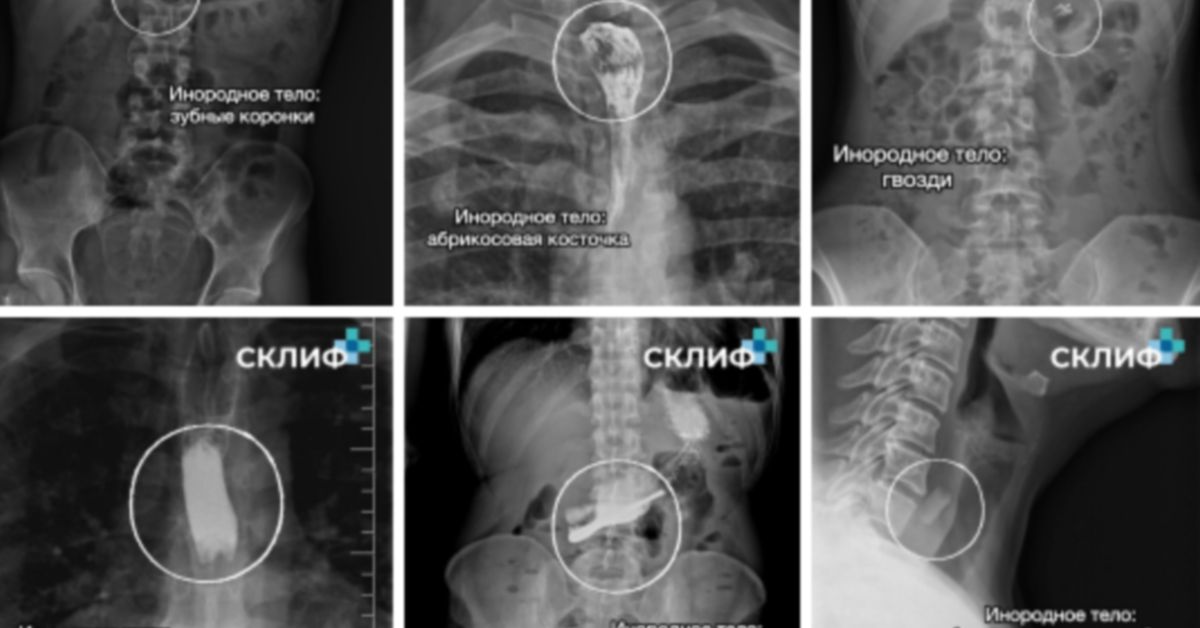

Медики Склифа рассказали: что именно инородное извлекали из москвичей в прошлом году